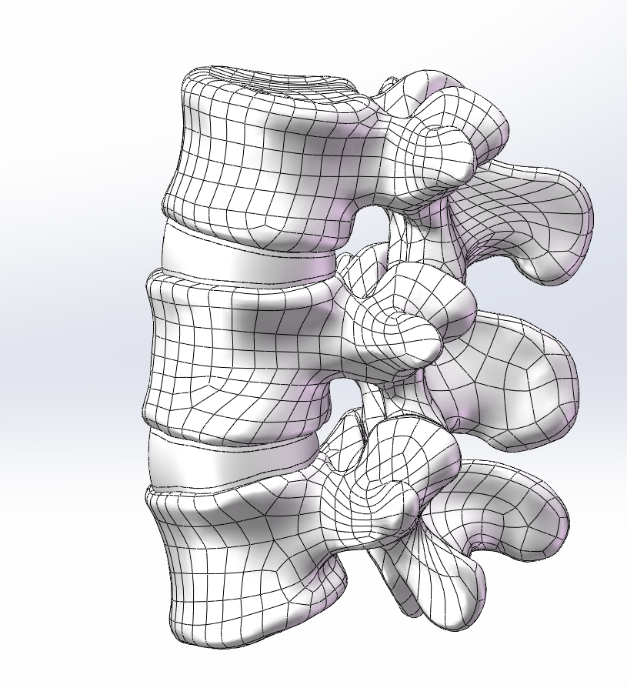

选取一名27岁青年男性志愿者在我院行腰椎螺旋CT扫描�����,扫描平面为���:第十二胸椎椎体至尾椎末端���,扫描厚度为0.625mm���,得到二维断层CT图像489张��,以DICOM格式进行储存���,导入计算机服务器�����。使用Mimics 19.0图像生成和编辑处理软件��,直接读取 DICOM格式的CT扫描数据进行三维重建���,见图 10����。根据软件中不同的灰度值来区分不同的组织����,用 Mimics 软件的阈值分割及区域增长功能画出腰椎(L3-5)����,不同的锥体用不同的颜色区分���,最后用图像填充功能填补图像中的空洞���,接着进行不同部位的三维重建��,得到仅包含骨性结构(L3-5)的模型��。将Mimics 软件得到的模型以STL格式模型文件导入Geomagic wrap2017软件中���,抹去模型钉状物和多余特征��,然后对模型进行优化光滑处理�����,将L3-5光滑处理后的每个锥体进行复制���,再将光滑后的模型在精确曲面中进行网格划分����,并进行构建曲面片及修理曲面片����,最后合成三维实体模型����,见图11�����。此时将复制的每个椎体模型外层向部件内部偏移2mm�����,内部充当松质骨��,外部的则定义为皮质骨����,椎弓根后部统一由皮质骨组成�����。随后将模型以STEP格式文件导入Solidworks2020软件中生成L3-5的实体模型零件��,并在模型零件中构建椎间盘��、髓核����、上下终板和软骨����,完成的实体模型���,此时的模型为单纯的正常腰椎三维几何模型���,各结构并未赋予材料属性与网格划分����,见图12�����。将模型导入ANSYS软件中���,随后对模型中皮质骨���、松质骨���、软骨����、终板���、纤维环���、髓核赋予相应的材料属性赋值���,尽可能地还原各组织材料的生理状况�����,提高模型的可靠性���。定义关节突关节面为 Frictional����,摩擦系数设为0.1��。在connections中建立spring模块���,模拟前纵韧带����、后纵韧带���、黄韧带��、棘间韧带���、棘后韧带���、横突间韧带及关节囊韧带��,各韧带对应刚度赋值��。建立完成后�����,对模型进行mesh操作构建网格���,见图13����。

图 12 Geomagic 图 13 ANSYS